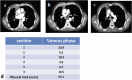

Background: Malignant pleural mesothelioma is the most common primary tumor of the pleura. The unique growth pattern of malignant pleural mesothelioma makes it difficult to apply the Response Evaluation Criteria for Solid Tumors (RECIST). Hence the need to use modified RECIST (mRECIST) criteria, as they better fit the unique growth pattern of malignant pleural mesothelioma. The thickness of the tumor perpendicular to the chest wall or mediastinum is measured at 2 points at 3 separate levels at least 1 cm apart on chest CT scans, and summed to obtain a one-dimensional pleural measurement. The same criterion has also been used to assess response to treatment. RECIST 1.1 represents a further update, taking into account new concepts such as revised minimum dimensions for lymph nodes and an approach to lesions that become non-measurable. Based on experience and published literature, the hypothesis of merging the 2 above-mentioned criteria in mRECIST 1.1 for mesothelioma and the use of iRECIST for the application to immune-based therapies (iRECIST) was considered. Purpose: Support the importance of studying pleural mesothelioma in a reliable and reproducible way, through a scrupulous methodology, applying the mRECIST1.1 and iRECIST criteria. Conclusions: Adoption of a standardized study metodology can make the study of PM reproducible and correct.